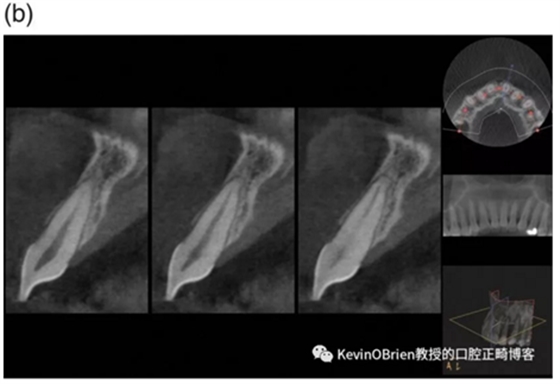

我們都熟悉正畸誘導(dǎo)性牙根吸收(Orthodontically Induced Root Resorption, OIRR)。一些研究把牙根吸收量與幾個(gè)可能原因聯(lián)系了起來(lái),例如治療持續(xù)時(shí)間,矯治器類(lèi)型以及施加的力。雖然這些研究給我們提供了有用的信息,但其大多數(shù)都采用了2D的頭顱側(cè)位X線片。CBCT影像的出現(xiàn)使得對(duì)OIRR的更精確測(cè)量成為可能。因此,作者們做了一項(xiàng)新的研究去探究這個(gè)問(wèn)題:

“用CBCT成像測(cè)量的OIRR的平均值是多少?”

他們選定了30篇文章,其中6篇是RCT,6篇是前瞻性非隨機(jī)化研究,還有18篇是回顧性研究。這些文章包含了年齡從11.4歲到26.6歲的1219位患者。

總之,我覺(jué)得我們能慎重地得出結(jié)論:當(dāng)使用CBCT測(cè)量OIRR時(shí),吸收的平均值是0.6-0.8mm。這是一個(gè)令人安心的小值。